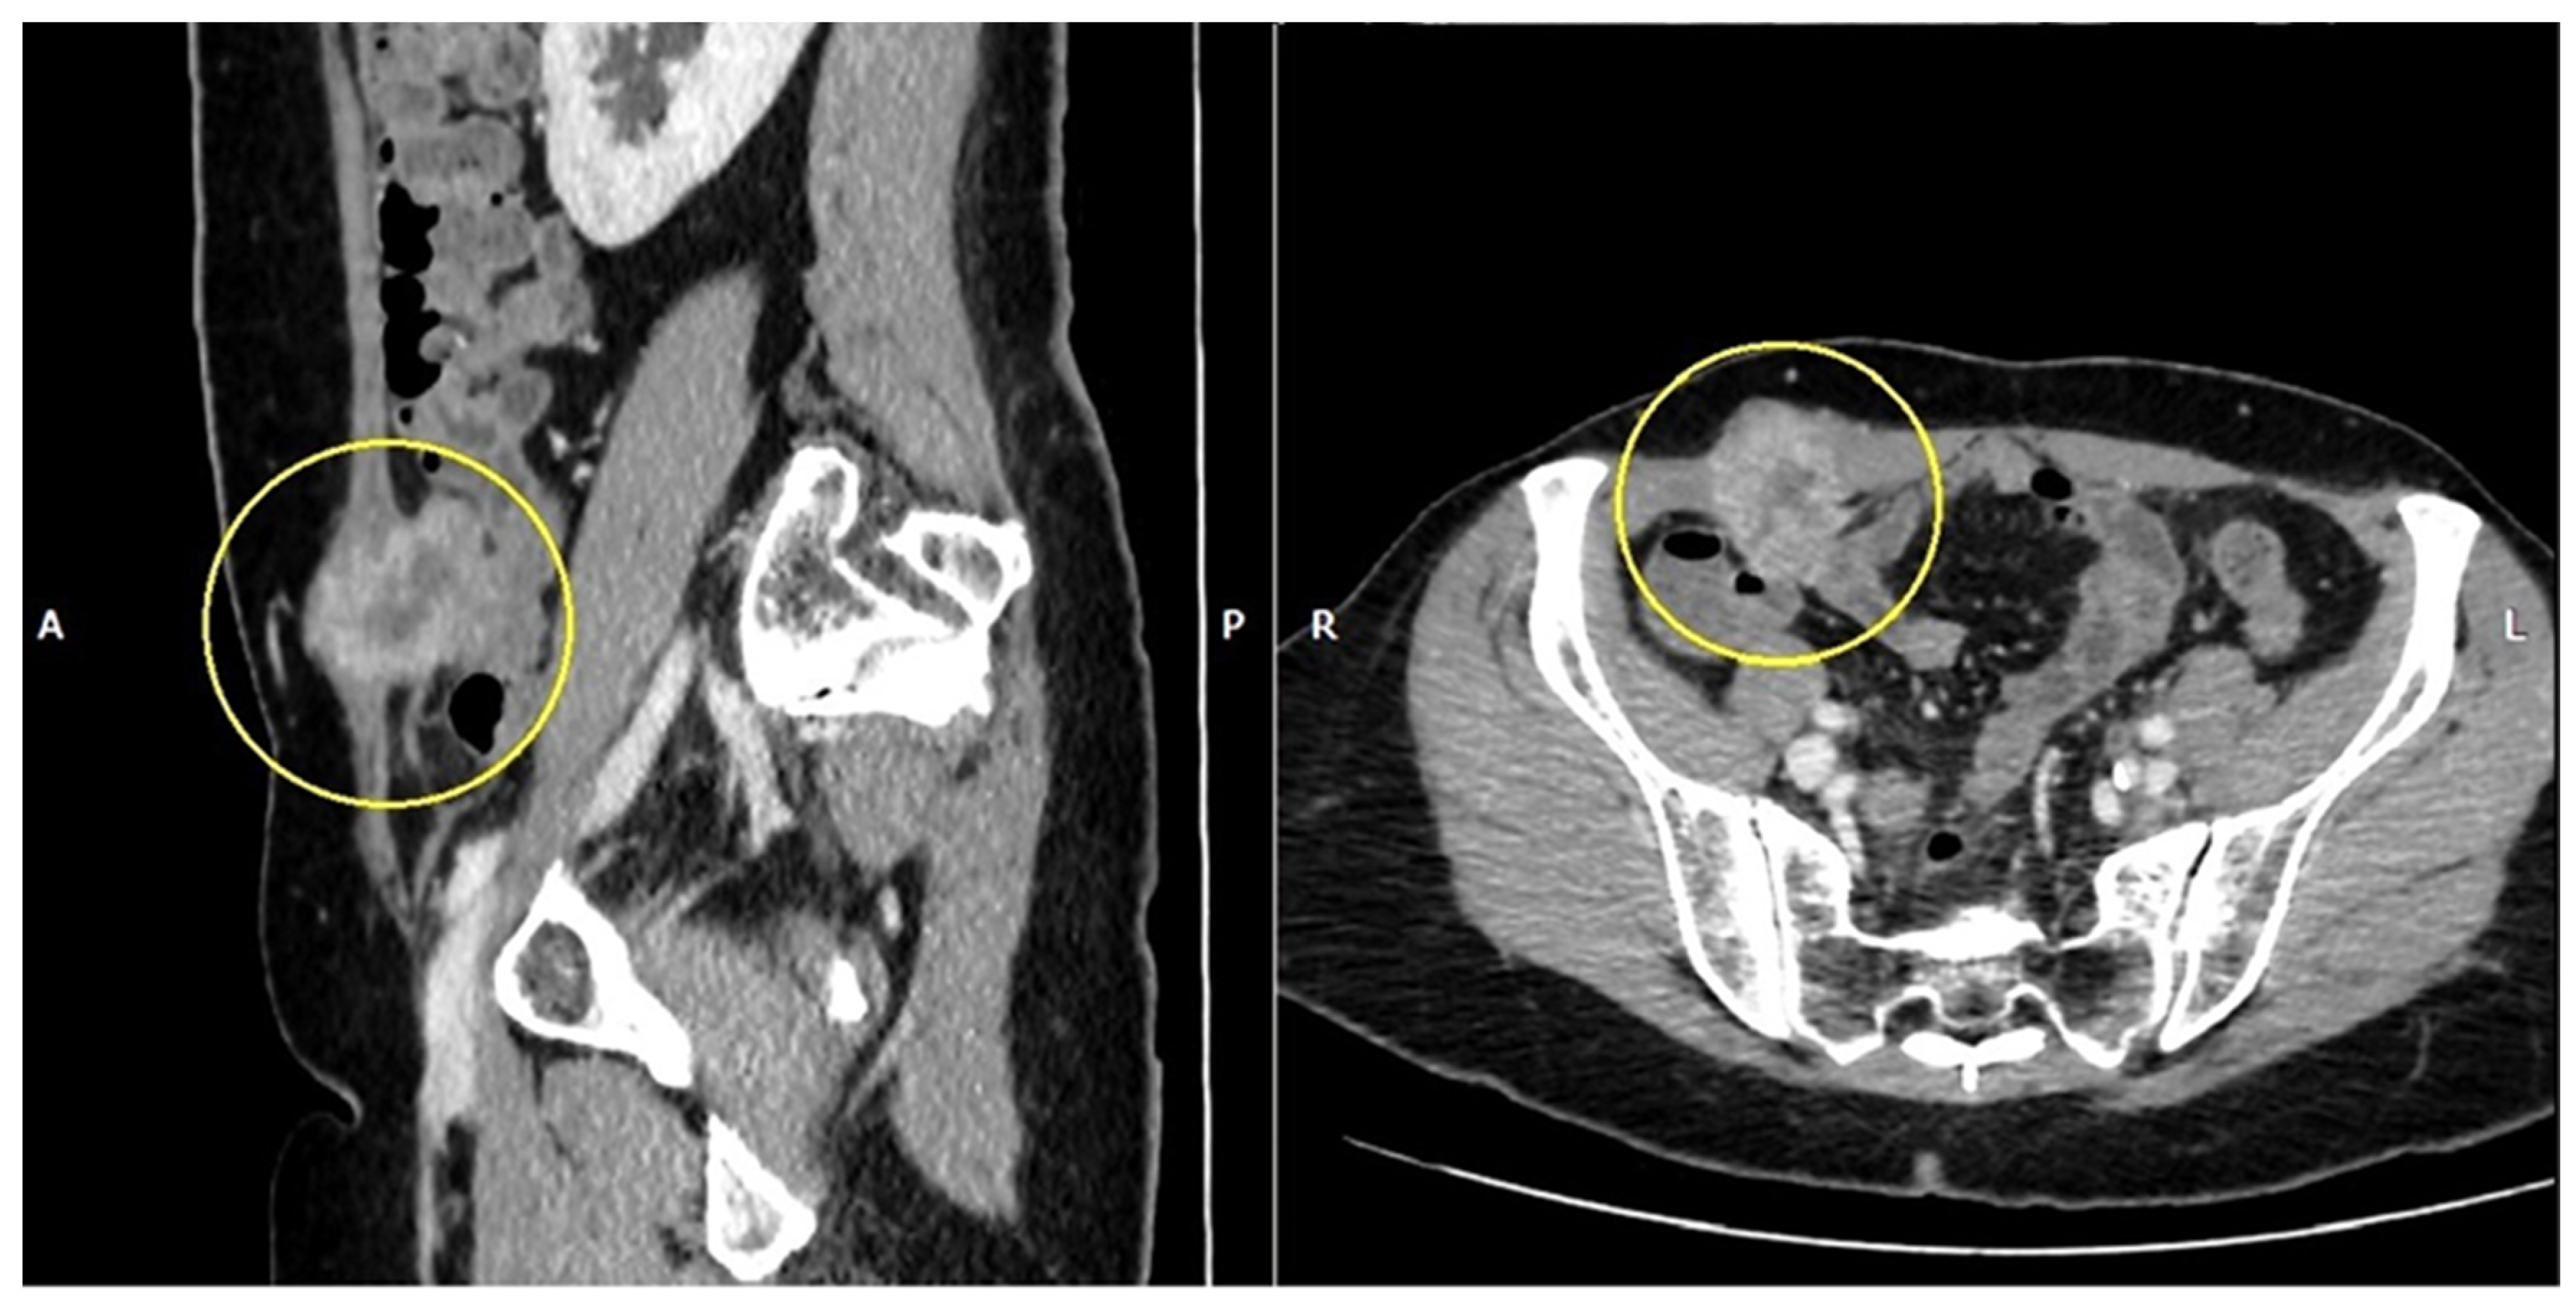

2. Case Description